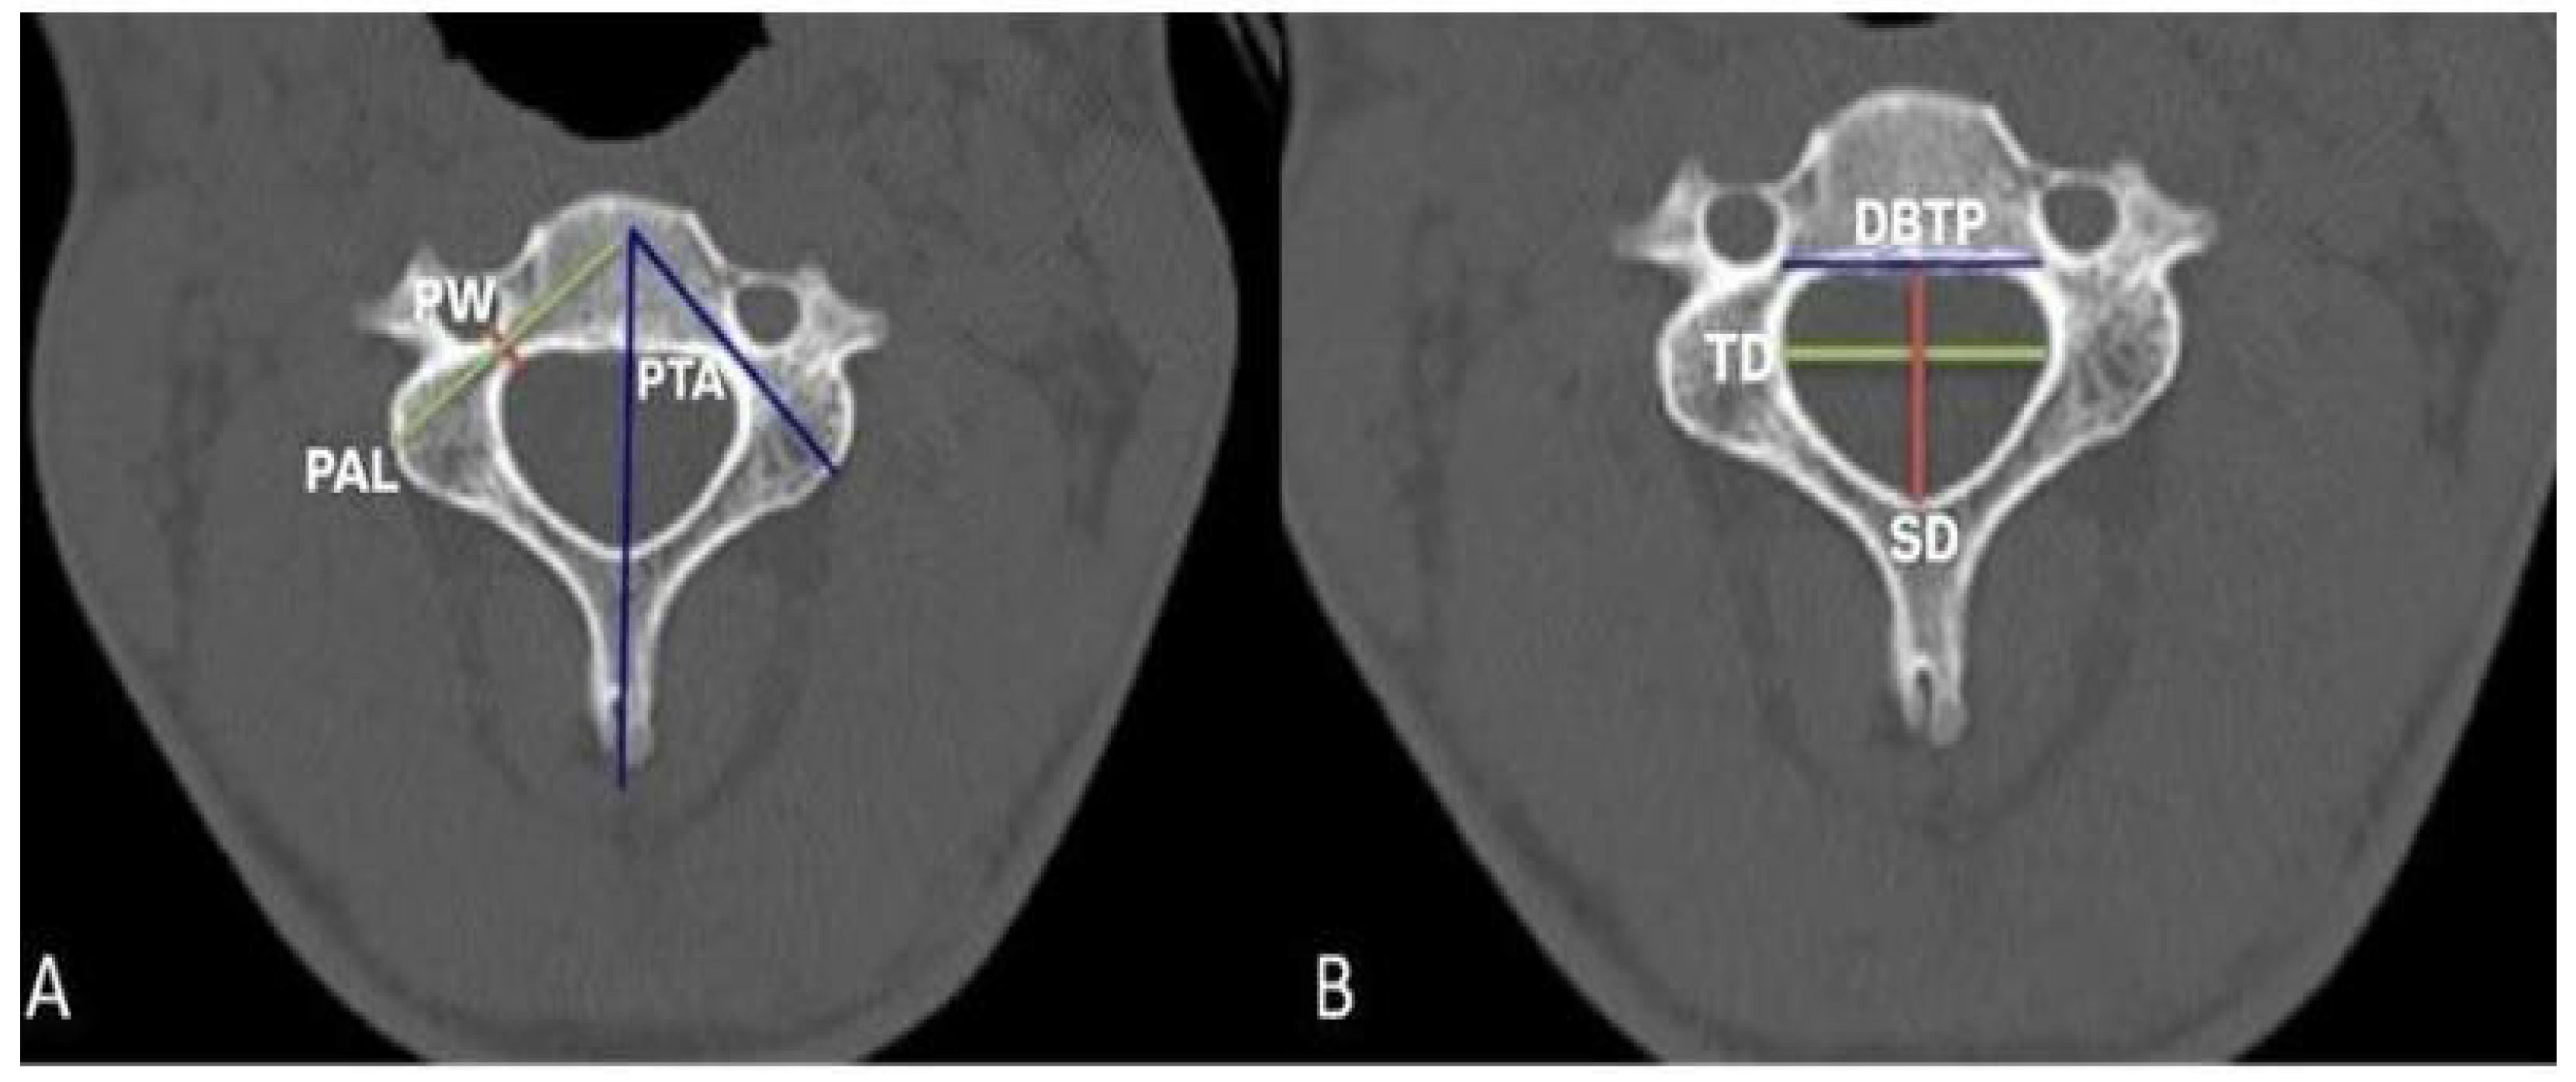

2. Materials and Methods